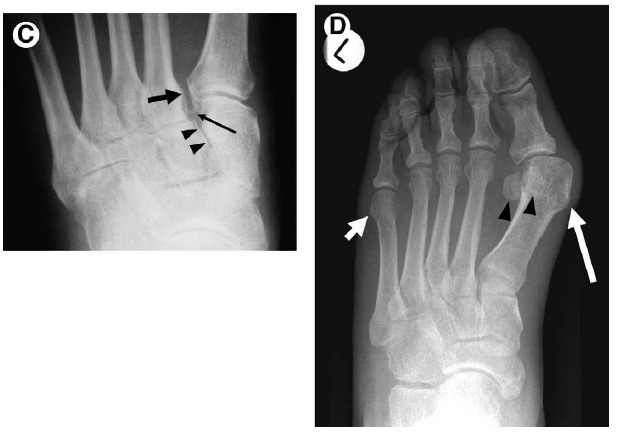

Figure 5 Fractures associated with ankle sprain. Avulsion fractures, particularly at the lateral malleolus, are common in the

setting of ankle sprain. Occasionally overlooked are sites of other fractures, including the following.

(A) Dorsal capsular avulsion. Lateral view of the foot demonstrates a curvilinear calcification dorsal to the talar head (arrow) representing a capsular avulsion. These may also occur at the navicular bone.

(B) Extensor digitorum brevis avulsion. Oblique view of the ankle shows thin calcification (arrow) adjacent to the anterolateral calcaneus consistent with an avulsion fracture from the origin of the extensor digitorum brevis tendon.

(C) Fifth metatarsal base fracture. AP view of the fifth metatarsal base in a skeletally immature patient shows a longitudinally directed, rounded ossification center (arrow) as well as a transversely directed avulsion-type fracture (arrowheads). Avulsion-type fractures in this location typically extend to the tarsometatarsal articular surface, whereas Jones-type fractures are more distal, occurring at the proximal shaft.

(D) Lateral talar process fracture. A fracture of the lateral talar process (arrow), also called a “snowboarder’s fracture,” is seen on this AP view of the ankle. These fractures are commonly missed and can be a source of chronic pain after a severe ankle sprain.

(E) Anterior process fracture of the calcaneus. Lateral view of the ankle shows discontinuity of the anterior calcaneal process (arrow). Like the snowboarder’s fracture, this injury is often missed on initial eval‎uation, resulting in chronic pain.